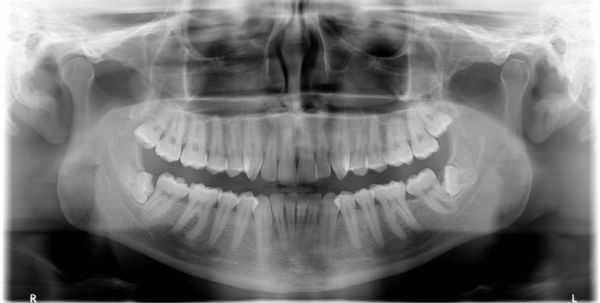

Дополнительные методы обследования: было проведено диагностическое рентгенологическое исследование. При анализе внутриротовой контактной рентгенограммы зуба 1.5 отмечался очаг разряжения костной ткани в области верхушки корня зуба 1.5 (рис. 2). Рис. 2. Внутриротовая контактная рентгенограмма зуба 1.5 до лечения. При проведении электроодонтометрии зуба 1.5 было получено значение более 100 мкА. При проведении термометрии зуб 1.5 не реагировал на холодовой и тепловой раздражители.